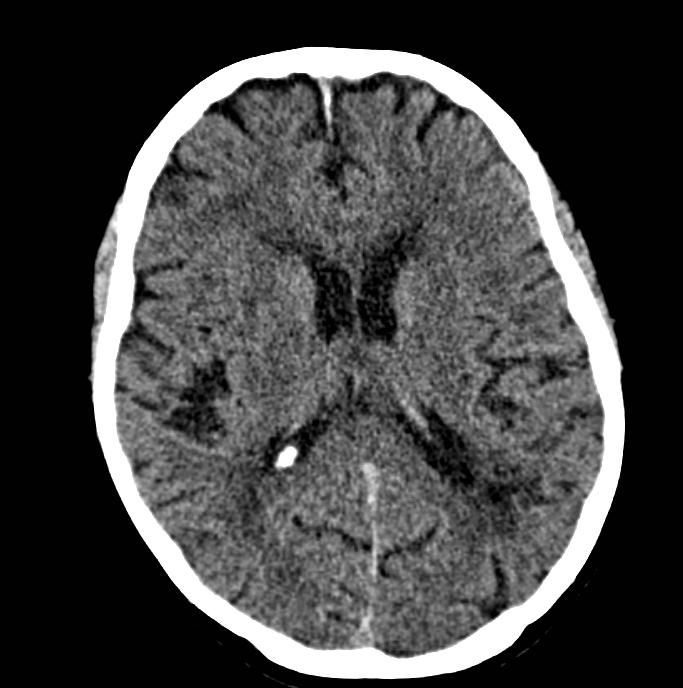

Oude, met name periventriculaire, afwijkingen, links meer dan rechts, met opvallend oude infarcering links parieto-occipitaal. Geen bloeding